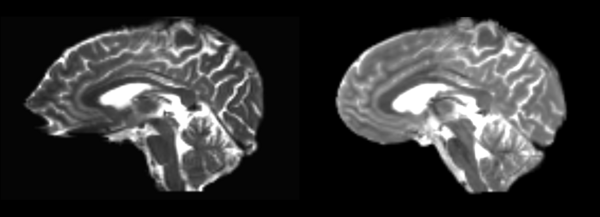

Linear

- 53-t2 -> 31-t1 = lin1

- lin1 -> 53-t2 = lin2

The image shows lin2 and 53-t2 side by side. The image shows there appears to be some change beyond loss of detail, possibly a L-R shift in the front.